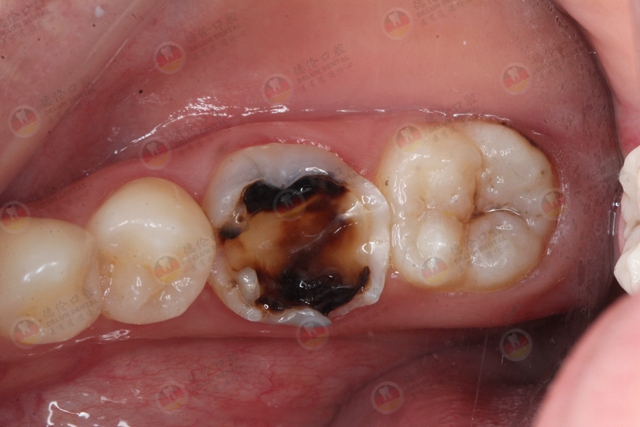

3.深龋:指已发展到牙本质中层或深层的龋坏。深龋临床上多有明显龋洞形成,龋洞内含有大量软化牙本质或食物残渣。

龋齿破坏了牙釉质,侵入牙本质危害会很大,牙齿遇冷、热、酸、甜等刺激后,都会感到疼痛,临床上可见牙齿上有呈黑褐色洞形成。当龋齿接近牙髓时,细菌及毒素侵入牙髓,引起牙髓炎症和自发疼痛,除了引起无法忍受的疼痛外,细菌和毒素还会顺着根管通道进入颌骨,导致根尖发炎和骨髓炎,牙齿松动,面颊肿胀,以及全身发热和不适。